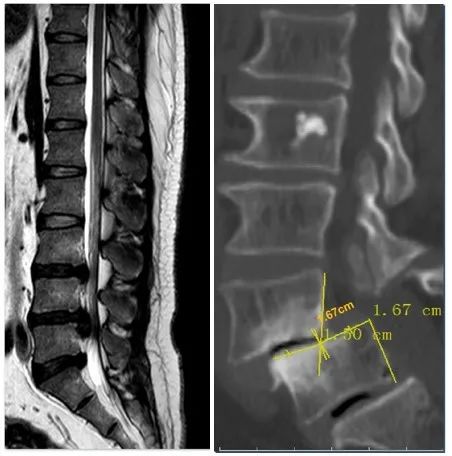

左图 :腰椎间盘突出症;右图:腰椎滑脱症